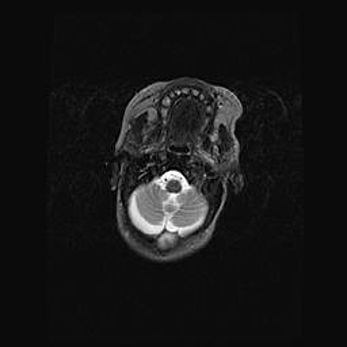

Аномалия Денди-Уокера – это порок развития головного мозга, для которого характерна триада симптомов: гипотрофия или аплазия червя мозжечка и/или полушарий мозжечка, расширение четвёртого желудочка с формированием ликворной кисты задней черепной ямки, гипертензионная гидроцефалия различной степени.

Гипоплазия мозолистого тела относится к дефектам внутриутробного этапа развития мозговой ткани, возникающим в процессе закладки структур головного мозга, что происходит на начальных этапах развития эмбриона.

Аномалия Денди-Уокера. Признаки гипоплазии мозолистого тела.

Возраст: 5 месяцев 3 дня

Вес: 5550 г

Пол: мужской

Окружность головы: 39 см

Срок гестации: 40 недель